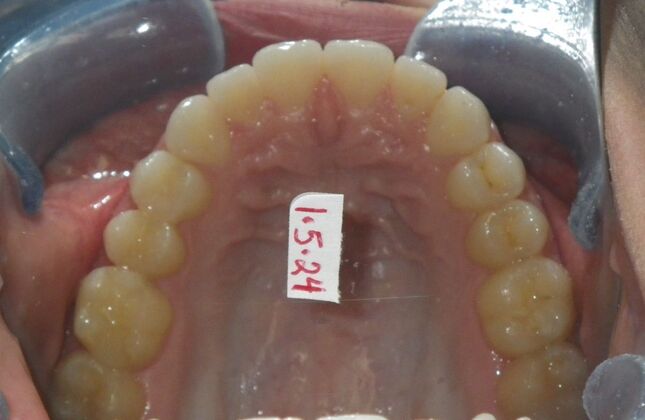

This patient was an awesome dental assistant for our practice and we were all very sad when she had to move closer to her home. She was very interested in correcting some minor spacing and rotations in her upper and lower anterior teeth and to decrease her overbite as well.Treatment took about 12 months, but we were pleased with the results and fabricated clear invisalign vivera retainers. We are still hoping one day she will return to be with us again.